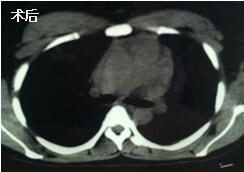

當(dāng)看到病人的CT等外院各項(xiàng)檢查時(shí),我頭皮發(fā)麻,心頭發(fā)怵:巨大的腫塊占據(jù)著整個縱隔,壓迫心臟,與血管關(guān)系密切,初步考慮侵襲性胸腺瘤、胸腺癌或淋巴瘤等,合并腎功能不全,無法完整切除,手術(shù)風(fēng)險(xiǎn)大,手術(shù)并不能提高病人長期生存率,換言之,小伙子等待的是生命的立即終結(jié)。

當(dāng)看到病人癥狀緩解,復(fù)查胸部CT幾近完美,我們那種自豪感油然而生。偶爾去治愈,常常去幫助,總是去安慰,我們深知,小伙子的人生之路并不長,只能深深祈禱他在我們的治療下能走得更遠(yuǎn)一些,能把剩下的日子走的更充實(shí)一些。而我們在能夠幫助人的時(shí)候,別一味地去安慰,永不言棄,是我們這一群胸外人堅(jiān)貞的信念。